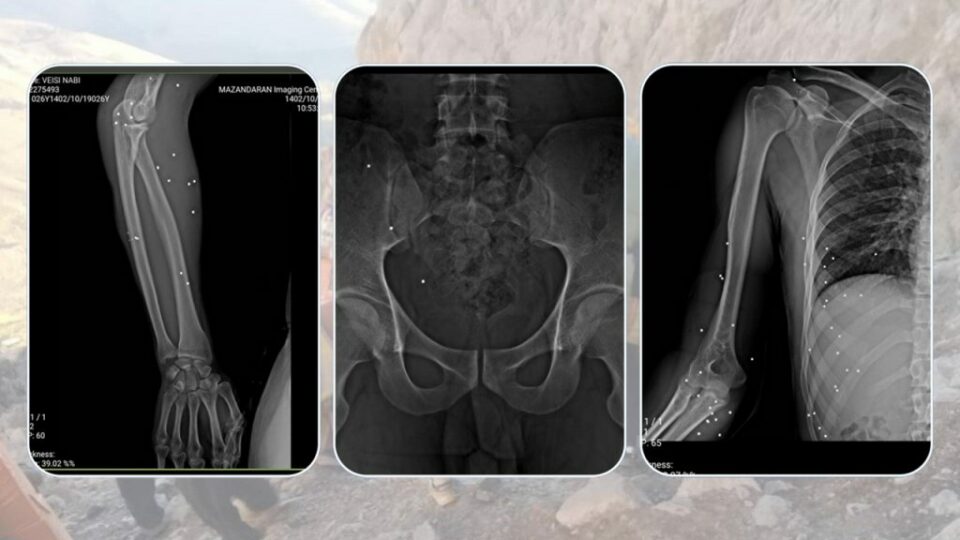

بهپێی ڕاپۆرتی كۆڵبهرنیووز، ڕۆژی چوارشهممه ٢٠ی بهفرانباری ١٤٠٢، كۆمهڵێك كۆڵبهر كهوتوونهته بۆسهی هێزهكانی ڕژیم له سنووری نهوسوود و ڕاستهوخۆ تهقهیان لێكراوه. له ئاكامی ئهو هێرشهدا، كۆڵبهرێكی خهڵكی جوانڕۆ به ناوی “نهبی وهیسی” بهسهختی بریندار بووه. بهپێی زانیارییهكان، جهستهی ئهو كۆڵبهر له سێ لاوه فیشهكی بهركهوتووه و ئێستا له نهخۆشخانهی تاڵقانی كرماشان لهژێر چاودێری پزیشكی دایه.